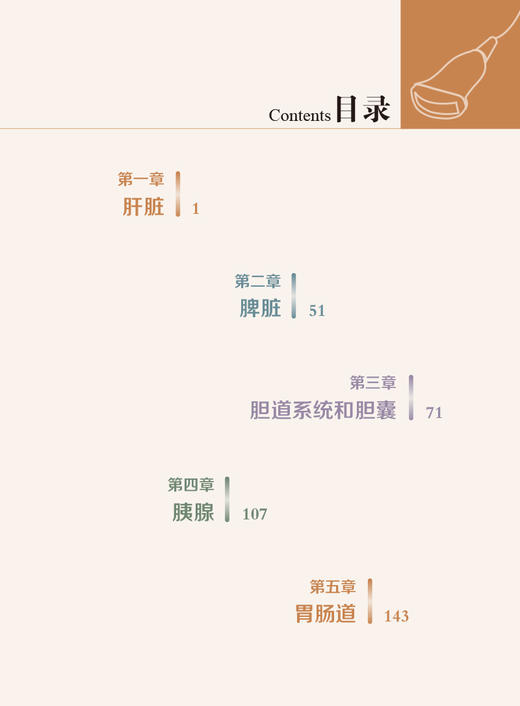

超声诊断学 第5版 消化系统分册 梁萍等译 肝脏脾脏胰腺胆道系统等脏器检查 超声影像诊断技术 基本技能规范 科学技术文献出版社